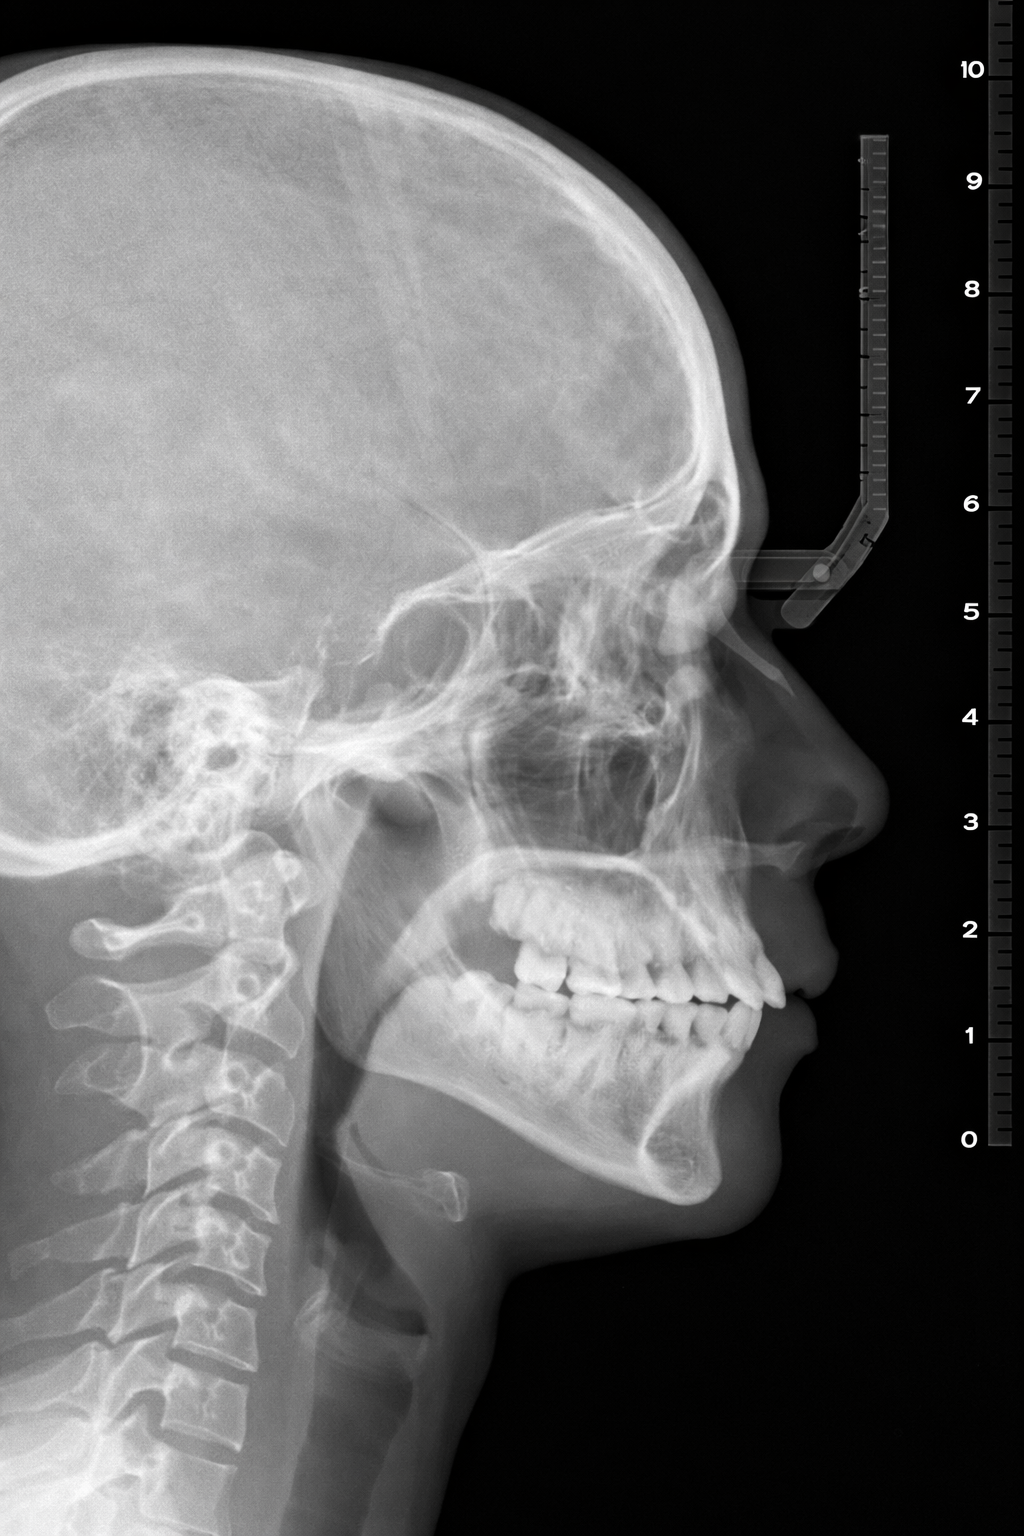

• X-ray cephalometry เป็นภาพเอกซเรย์ด้านข้างศีรษะ ใช้ประเมินความสัมพันธ์ของโครงสร้างใบหน้า เช่น ขากรรไกร คาง เพดานอ่อน ลิ้น และตำแหน่งของกระดูกไฮออยด์ การตรวจชนิดนี้ช่วยให้แพทย์พิจารณาได้ว่า โครงสร้างใบหน้าอาจเป็นปัจจัยร่วมของการนอนกรนหรือ OSA หรือไม่

• โดยทั่วไป X-ray cephalometry เหมาะในผู้ป่วยที่มีลักษณะคางถอย ใบหน้าแคบ หรือการสบฟันผิดปกติ ข้อดีคือ ใช้เวลาสั้น ค่าใช้จ่ายไม่สูง และได้รับรังสีในระดับต่ำ แต่ไม่สามารถบอกความรุนแรงของ OSA ได้ และไม่ใช้แทน sleep test